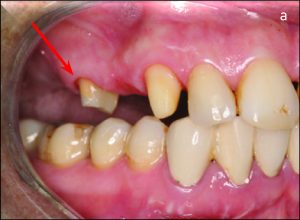

Crown restorations that are joined together provide fixed splinting. When force is applied, the goal is for the teeth to resist one another. Anteroposterior resistance is increased when the posterior support teeth are splinted. The posterior restoration needs to incorporate multiple anterior teeth in order to be effective in the mediolateral direction (Figure 10-12).

Fixed splinting in such a situation weakens the support of the healthy tooth instead of strengthening the weak abutment tooth. RPD further complicates the situation and accelerates tooth loss. The best treatment option in this case might be to extract the weak abutment tooth and use the adjacent abutment tooth as RPD primary abutment.